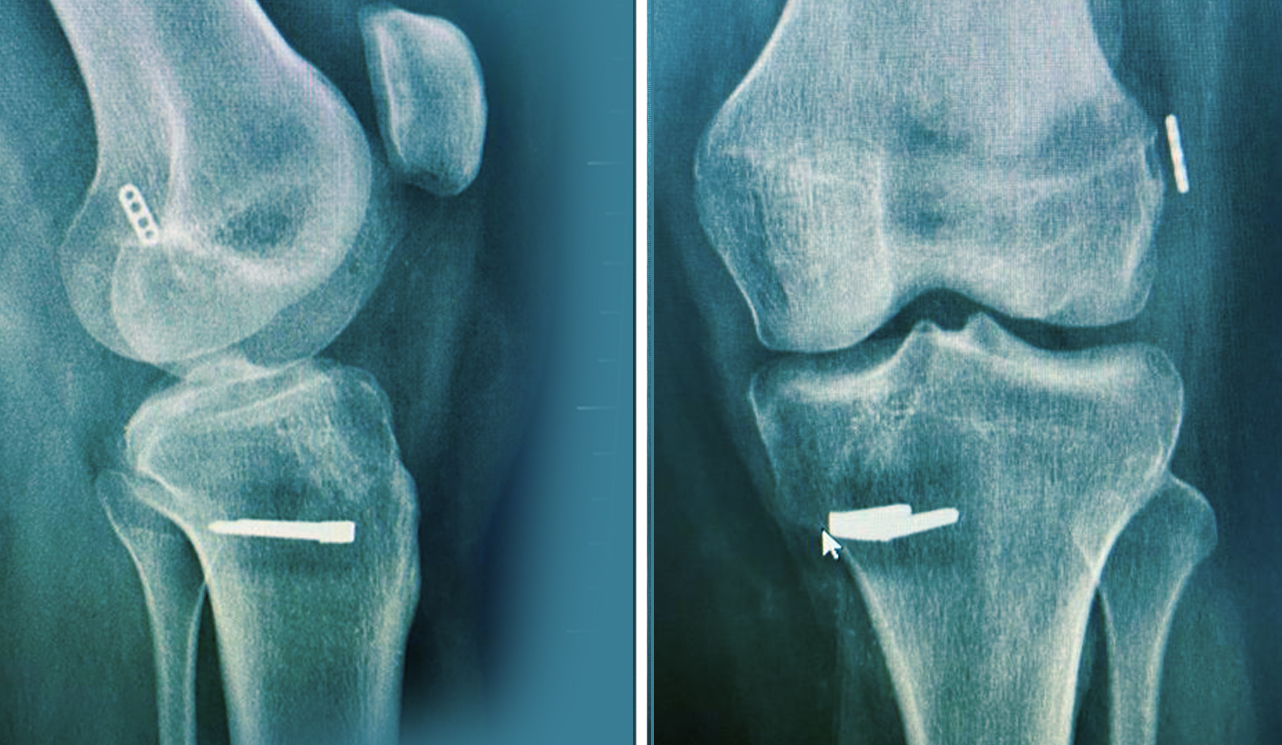

Vücudun çok sayıdaki dokusu özellikle de kas ve tendonlar koşu esnasında ciddi olarak etkilenir. Hemen bütün kas gruplarının aktivitesi artar. EMG çalışmaları kuadriseps kasında % 172, hemstringlerde % 86, tibialis anterior kasında % 56 ve triseps ka sında ise % 95 oranında aktivite artışı göstermektedir.

Koşucularda problem alt ekstremitelere art arda binen yüklerden kaynaklanır. Her adımda vücut ağırlığının 1,5-5 misli yük ayaklara etki etmektedir. Koşan bir erişkinde her 1500 metrede, her bir ayağa 150-200 tonluk bir ağırlık binmektedir. Bütün bu yüklenmeler sonucu dokularda patolojik değişikliklerin ortaya çıkması mümkün olmaktadır